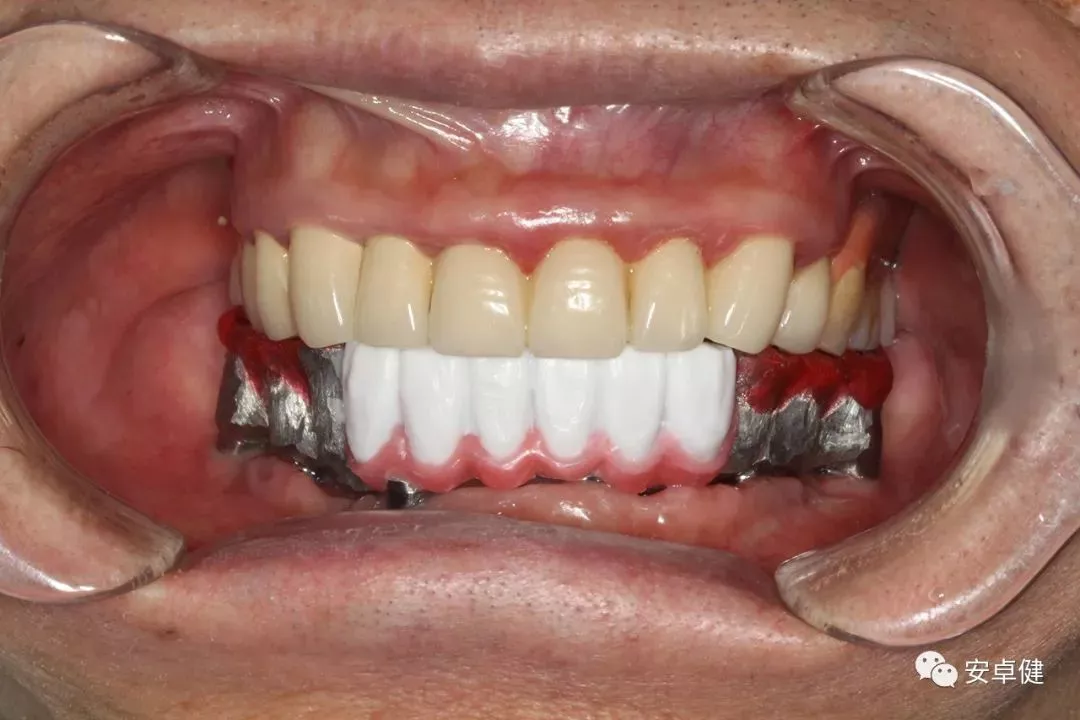

戴最终修复体正面咬合照

▷ 永久修复

患者术后16个月:

• 于口内试戴原厂纯钛切削一体式桥架,并检查前牙排蜡外形及后牙咬合关系;

• 聚合瓷烤塑制作最终修复体;

• 为减少牙面磨耗,于后牙区制作360度防裂纯钛金属带;

• 试戴满意后,二级螺丝加力至15N;

• 特氟龙封闭螺丝孔,光固化复合树脂封闭上方螺丝通道,完成最终固定式种植义齿修复;

• 修复体外形能够正确恢复面下1/3高度及侧貌;

• 患者可获得较为稳定的咬合关系,并满足其咀嚼功能的需求;

• 患者42、46部位牙龈退缩,缺乏足够的角化龈,为方便后期清洁维护,选择穿龈较高的龈上肩台;

• 口内观察,修复体边缘金属基台颜色暴露,但由于其处于下颌后牙非微笑暴露区,故对临床整体美观效果的影响在患者可接受范围内。